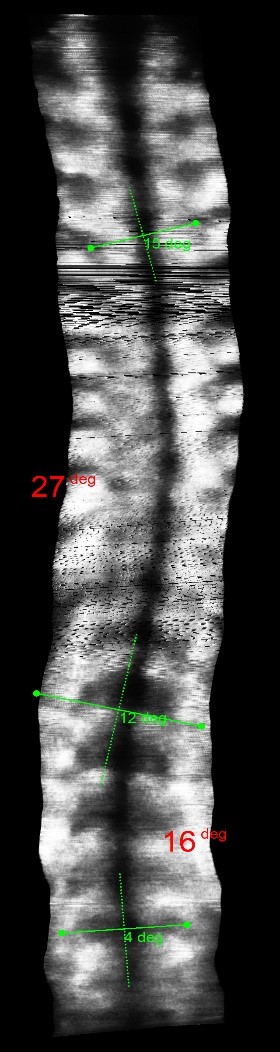

The clinical test results show that the SCN800 series is highly consistent with the X-ray, with a linear correlation of 0.94, similar results have also been published in SCI articles (Lee TT, Lai KK, Cheng JC, Castelein RM, Lam TP, Zheng YP. 3D ultrasound imaging provides reliable angle measurement with validity comparable to X-ray in patients with adolescent idiopathic scoliosis. Journal of Orthopaedic Translation. 29:51-59, 2021).

In our clinical trials and studies, we measured two angles to facilitate comparison. X-rays can actually show 3 to 4 angles, some in the neck and bottom area. Ultrasound images can also measure angles near the neck like an X-ray.

The following images compare 5 ultrasound and X-ray clinical measurement examples: